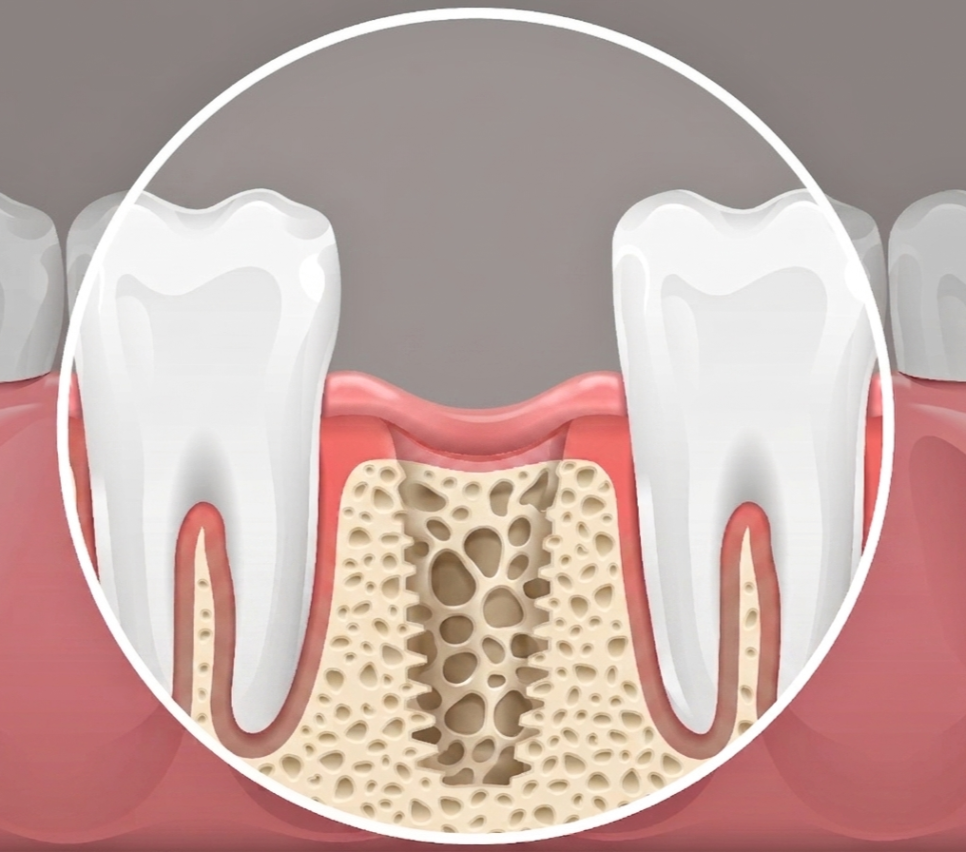

- 임플란트 주위염

잇몸 사이 세균으로 인해 뼈가 녹아내린 경우

임플란트 주위염으로

기존의 흔들리는

임플란트를 제거했을 경우

세균으로 인해 오염되어 파괴된

주변 조직의 환경 개선이

우선적으로 시행되어야 합니다.